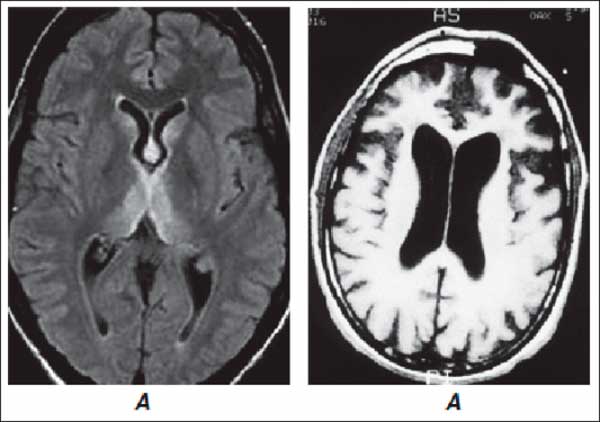

Диагностика заболевания включает в себя проведение анализов крови, прохождение обследования пациентом: МРТ мозга, ЭЭГ (электроэнцефалограмма), УЗИ сосудов шеи и головы. В зависимости от проявляемых симптомов, результатов исследования, степени тяжести энцефалопатии головного мозга врач назначает комплексное лечение.

- Компьютерная томография и МРТ показывают наличие новообразований, признаки инсульта, воспалительных заболеваний, рассеянного склероза, болезни Альцгеймера, Паркинсона, сосудистых нарушений.